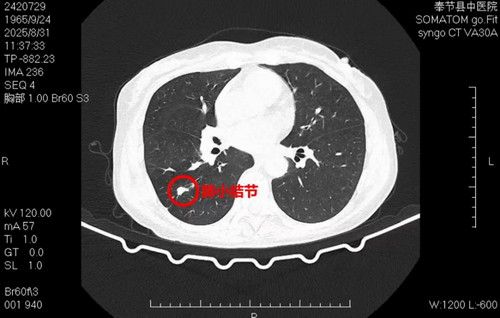

近日,奉节县中医院肺病科成功完成了首例细支气管镜联合气管内超声引导下的肺结节精准活检术。

该患者为一名胸部CT提示肺结节的中年女性,患者家属担心为恶性病变。为确定结节性质,在重庆医科大学附属第二医院支医专家赵燕教授及山东省滨州市阳信县人民医院支医专家冯玉霞教授的指导下,肺病科团队为患者实施了此次检查。

术中,通过细支气管镜的灵活深入,结合气管内超声的精确定位,成功对目标病灶进行了取样,整个操作过程顺利,患者术中及术后均未感到任何不适。术后病理结果显示为慢性炎症反应,为排除肿瘤性病变提供了关键依据,使患者免除了不必要的担忧和更具创伤性的检查。